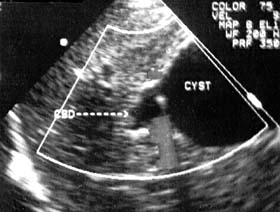

Trả lời:Bạn hãy bình tĩnh và hay xem lại các kết quả siêu âm cũng như các kết quả về xét nghiệm của bạn liên quan đến bệnh sán lá gan lớn như ELISA, bạch cầu eosin, …Chúng tôi nghĩ rằng, hiện nay với bệnh sán lá gan lớn thì thuốc điều trị đặc hiệu loại Triclabendazole vẫn còn rất hiệu quả, hình như với thông tin chủ quan của chúng tôi trên y văn và trong thực hành lâm sàng của chúng tôi điều trị trên 10.000 trường hợp thì chưa có trường hợp nào biểu hiện không đáp ứng cả, dù một số trường hợp chúng tôi phải điều trị đến liều thứ 2 hoặc thậm chí khoảng 0.5% điều trị đến liều 3 vì ổ dịch quá lớn và nặng. Chúng tôi rất tiếc không biết là trước khi điều trị bệnh sán lá gan lớn này thì kích thước tổn thương cũng như đặc điểm thương tổn gan của bạn như thế nào, cân nặng của bạn là bao nhiêu vì chúng tôi biết một số bệnh nhân dù cân nặng lớn hơn 50 kg, thậm chí trên 60kg mà các thầy thuốc vẫn điều trị chỉ có 2 viên tương đương 500mg thì không đủ liều cho điều trị cho bạn, điều này sẽ dãn đến thất bại điều trị do dùng dưới liều, bạn nên cho chúng tôi biết các thông tin cụ thể (có thể gọi cho chúng tôi theo số điện thoại BS Huỳnh Hồng Quang_0905.103496 để trả lời chi tiết hơn cho bạn).

Mặc khác, khi bạn bị sán lá gan thì triệu chức đau tức vùng gan là điều dễ hiểu, song sau khi điều trị bạn lại còn một số triệu chứng như bạn mô tả là có thể, nhưng rất hiếm bạn ạ. Thân chúc bạn khỏe và thông tin phản hồi lại cho chúng tôi biết sớm nhé.